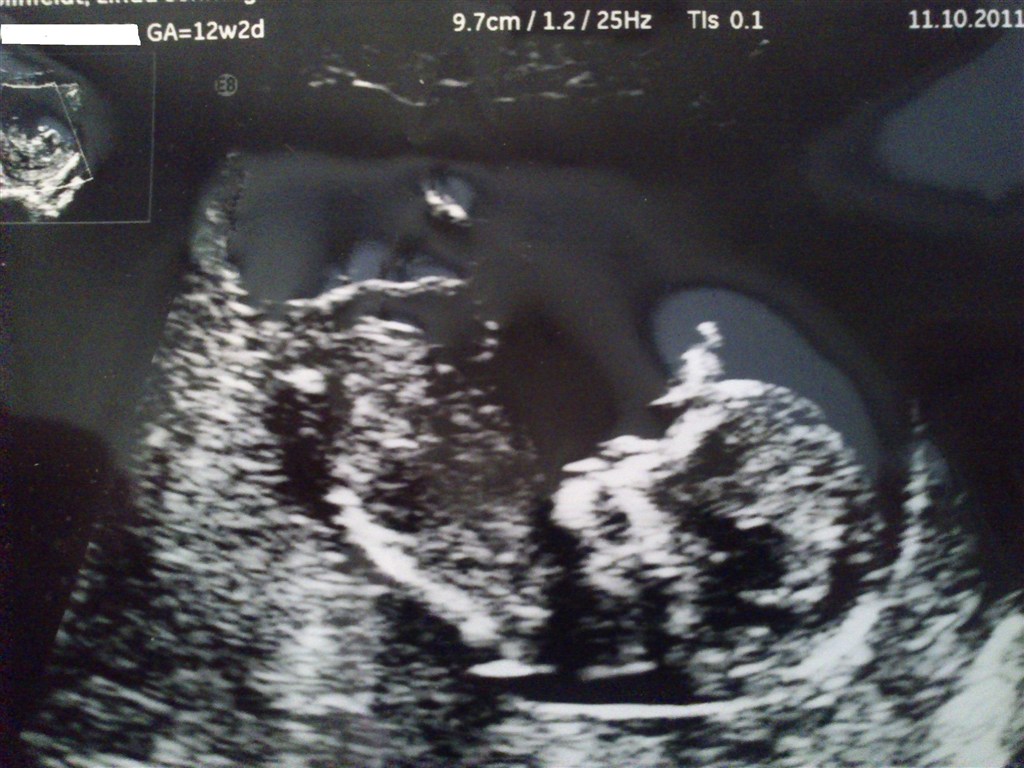

Jeg skal til misdannelsesscanning d. 8 dec. og jordmoder her d. 18 nov. Har lige været til kønsscanning på privatklinik idag. Det var ingen tvivl om at det var en lille dreng der lå derinde. En lille fodboldspiller er han, han sparkede helt vildt :O hehe